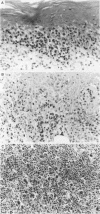

AIMS: (1) To assess the clonality of tumour cells in two patients with mycosis fungoides who subsequently developed Hodgkin's disease; and (2) to determine whether there is a clonal relation between these two disorders. METHODS: Cutaneous tissue samples involved by mycosis fungoides and lymph nodes involved by Hodgkin's disease from both patients were investigated by immunohistochemistry and the polymerase chain reaction. RESULTS: Mycosis fungoides tumour cells in both patients expressed multiple T cell associated antigens; Reed-Sternberg (RS) cells had the null phenotype. T cell receptor gamma chain genes were clonally rearranged in mycosis fungoides cells but not in RS cells, including variants, in both patients. In the patient with intermediate transformation to large cell lymphoma, immunoglobulin heavy chain genes were rearranged in the cutaneous tumour, but not in the lymph node involved by Hodgkin's disease. CONCLUSION: The divergent antigen expression and gene rearrangements observed in these two patients strongly suggest that Hodgkin's disease and mycosis fungoides are not derived from a single tumour cell clone.